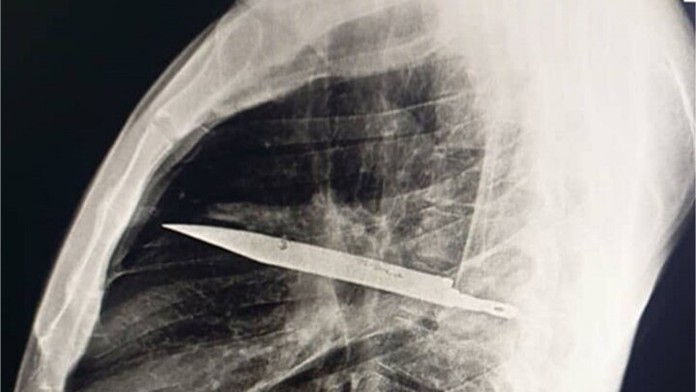

Muž mal v tele zabodnutý nôž osem rokov Zdroj: National library of medicine

V Tanzánii šokoval lekárov 44-ročný muž, ktorého vyšetrili po tom, čo sa mu na hrudníku začali tvoriť hnisavé rany. Röntgen ukázal niečo, čomu spočiatku ani neverili – v oblasti pľúc mal zabodnutý nôž, ktorý v tele nosil celé roky. Informoval o tom web Mirror.

Keď prišiel do nemocnice, mal v oblasti pod pravou bradavkou výrazne stvrdnutú pokožku a z rany mu vytekal zapáchajúci hnis. Po röntgene bolo jasné, že kovový predmet je stále v jeho tele. Pacienta okamžite poslali na operáciu, pri ktorej mu nôž vybrali.

Podľa lekárov prežil len vďaka tomu, že jeho organizmus si okolo noža vytvoril hrubú vrstvu tkaniva, ktorá zabránila vzniku smrteľného zápalu. Po ôsmich rokoch však tento obranný mechanizmus zlyhal a začali sa objavovať vážne komplikácie. „Aj keď sa pacient po operácii zotavil, nôž mohol kedykoľvek spôsobiť fatálne následky,“ upozornili lekári.